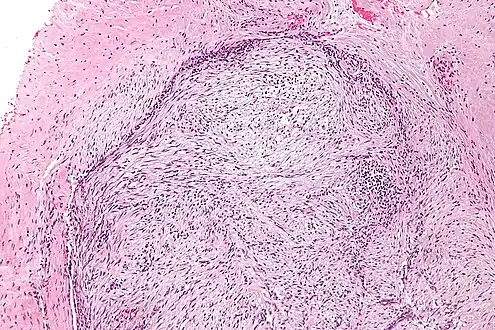

The microscopic histopathology of hematoxylin and eosin stained nodular fasciitis tumors (see above and three below figures) consists of spindle-shaped myofibroblastic cells (i.e. cells with features of smooth muscle cells and fibroblasts.).[9] These cells are in a myxoid (i.e. more blue or purple compared to normal connective tissue because of excessive uptake of the hematoxylin stain) or a collagenous (high content of collagen fibers) tissue background. The neoplastic myofibroblasts are arranged in whorls and/or short bundles. These cells may show high rates of replicating as judged by their mitotic index but these mitoses are normal in appearance. The tumor tissues often contain red blood cells, lymphocytes and giant osteoclast-like giant cells and may contain sites of bone-like tissue.[11] NF is sometimes classified into three subtypes based on its predominant histopathological pattern: myxoid or reactive (type I), cellular (type II), and fibrous (type III).[5] These patterns appear related to the duration of the lesion with the myxoid variant tending to have the shortest duration and the cellular and fibrous variants tending to have progressively longer durations.[15]Immunohistochemical analyses indicate that the cells in NF usually express smooth muscle actin, muscle specific actin, and vimentin proteins but generally do not express CD34, S-100 protein, desmin, trypsin, factor VIII, F4/80 (also termed macrophage-specific antigen), or HLA-DR1 proteins.[11] Uncommonly, the cells in NF tumors also express the CD68 (a histiocyte-specific marker) protein.[5]

Intermediate magnification